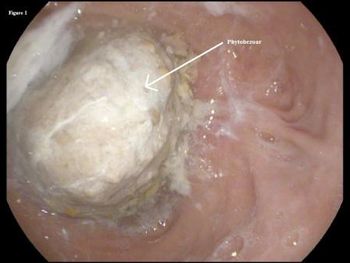

The types of digestive disorders are many, and the symptoms vary widely. This week's photo quiz offers a variety of presentations to test your diagnostic acumen.